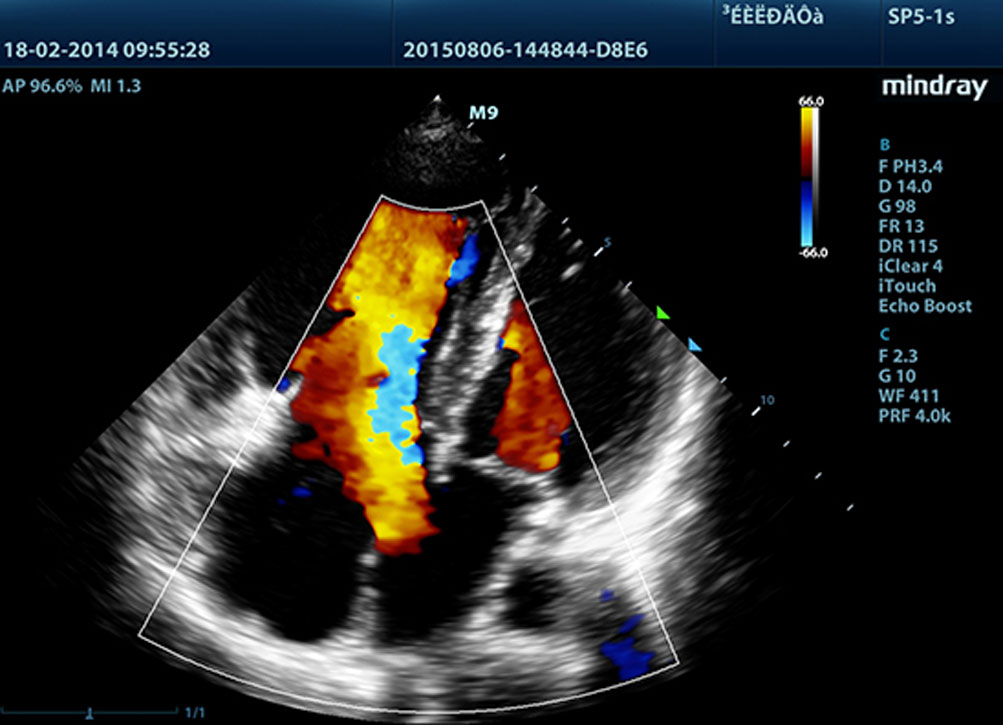

?? ?????? ?? LVO

M9? ???? ??? ?? ?? LV ????? ?? ?? ??? ?? ? ?? ??? ???? ??? ??? ?? ?? ???? ?????. M9? ?? ????? ??? ???? ??? ?? ?? ??? ?? ??? ???? ?????. ? ???? ???? ??? ?? ???? ? ?? ??? ?? ?? ???? ?? ?????.